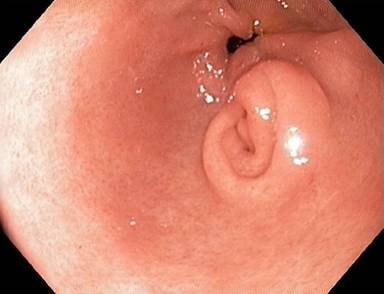

A 38-year-old male patient presented to the emergency room due to acute epigastric pain, nausea and vomiting. Physical examination revealed tenderness in the upper abdomen. Body temperature was 37.3°C. C-reactive protein was 113 mg/L (reference range: 0-3 mg/L) and his white blood cell count was raised (15.5 x109/L; reference range: 3.5-8.8 x109/L). Renal and liver function tests and serum pancreatic amylase were normal. He was otherwise healthy and was not taking any medications. Upper gastrointestinal endoscopy showed a subepithelial lesion in the gastric antrum (Figure 1). Abdominal computed tomography scan revealed a heterogeneous 4 cm malignant-looking lesion in the gastric antrum with suspected invasion of the perigastric fat (Figure 2). Endoscopic ultrasound (EUS) confirmed the presence of a subepithelial lesion in the antrum, that had heterogeneous appearance and involved all subepithelial layers of the gastric wall (Figure 3). An EUS-led fine needle aspiration (FNA) showed inflammatory cells only. The patient recovered symptomatically and blood tests normalized within 5 days. However, on the grounds of the imaging findings, malignancy could not be excluded and distal gastrectomy was performed. Histopathology of the surgical specimen confirmed the presence of ectopic pancreas in the gastric antrum (Figure 4a) but showed no cancer. However, there was both chronic and acute inflammation with neutrophil infiltration (Figure 4b). Twelve months following surgery he was asymptomatic.

Figure 1. Upper gastrointestinal endoscopy revealed a subepithelial lesion in the gastric antrum with endoscopic appearance consistent with an ectopic pancreas. |